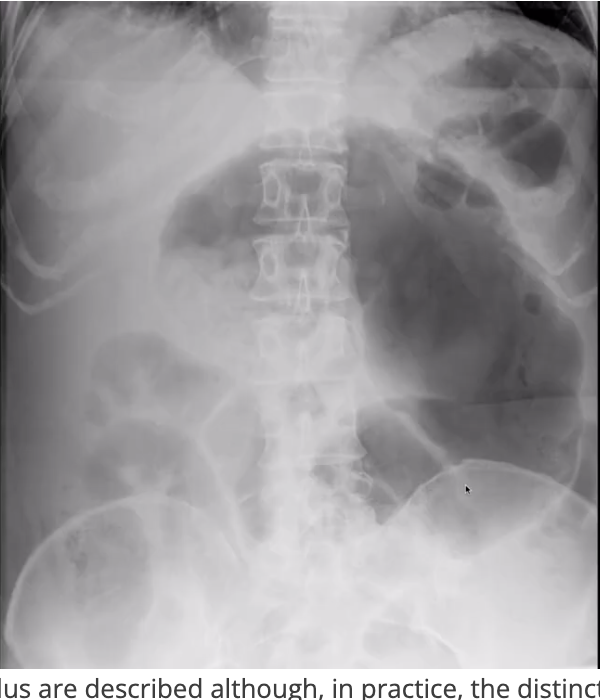

Thumbprinting of the bowel

concerning for severe colitis

ischemic colitis, UC, c. diff, etc